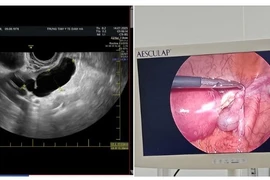

Khoa Phụ ngoại A5 - Bệnh viện Phụ Sản Hà Nội vừa tiếp nhận bệnh nhân 14 tuổi ở Hà Nội với tình trạng bị ra dịch âm đạo, đau bụng dưới và sốt. Qua thăm khám, bác sĩ chỉ định nhập viện do nghi ngờ viêm phần phụ hai bên.